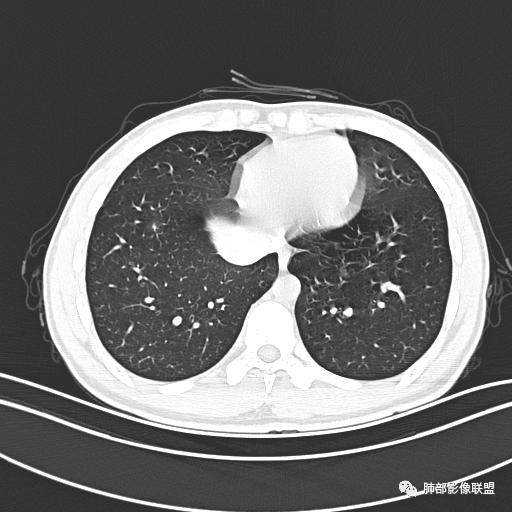

男,19岁

主  诉:发热、全身皮疹2天。

现病史:患者源于2天前受凉后出现发热,最高体温为38.5℃,且颜面部出现少量皮疹,无鼻塞、流涕、咳嗽、咳痰,未在意而未作特殊处理,次日全身皮疹逐渐增多至全身,伴轻度瘙痒,在当地卫生所给予抗病毒、抗感染治疗(具体用药不详)体温有所下降,但皮疹无明显消退,无腹痛、头痛,食欲无明显减退,为进一步诊治,遂于今日急来我院求治,患者目前精神尚可,体力正常,食欲正常,睡眠正常,体重无明显变化,大便正常,排尿正常。

小强:青年,发热,皮疹;双肺散在结节,周围磨玻璃,点晕征,疱疹病毒感染,鉴别荚膜组织胞浆菌,结核。 大雄:青年,急性起病,发热伴全身皮疹2天,抗病毒治疗体温有下降。双肺随机分布大小不等类圆结节,“点晕征”。考虑水痘-疱疹病毒(VZV)血播询问接触史,查体皮疹分布以及形态基本可诊断。 王开金江津中心医院呼吸科:青年男性,起病急,病程短,以发热,皮疹为首发症状,感染指标以单核细胞升高为主,胸部ct双肺多发结界,周围有晕,点晕表现,随机分布,同意於老师意见,水痘疱疹病毒血流感染累及肺。 王秀仙:双肺多发大小不等结节,周围有晕,边缘模糊,呈点晕征表现。青年,急性起病,发热伴全身皮疹2天,抗病毒治疗体温有下降。考虑疱疹病毒。鉴别荚膜组织胞浆菌。 傅昌瑜:19岁男性,发热、全身皮疹2天,单核细胞增高,双肺多发结节,结节边缘见边界不清磨玻璃影。点晕征+发热、全身皮疹+单核细胞增高——考虑水痘-带状疱疹病毒肺炎。 一切∮随缘:年轻男性,发热,皮疹两天,实验室,CRP,PCT增高,影像:双肺多发散在磨玻璃结节,边界欠清,大小不等,呈点晕征改变,以血管束周围分布为主,局部血管束略增粗,其它无明显改变,考虑:1:病毒性肺炎(水痘疱疹病毒?不知道皮肤有无改变)2:真菌(组织胞浆菌,血管侵袭性肺曲霉)3:GPA4:寄生虫(实验室没有看到嗜酸细胞增高) 赵山河:双肺散在结节,周围有晕,边缘模糊,呈点晕征表现。青年,急性起病,发热伴全身皮疹2天,抗病毒治疗体温有下降。考虑水痘—疱疹病毒感染。洪桥爱:青年男性,发热、皮疹2天,伴瘙痒,皮疹于面部首发,之后进展至全身,虽然没有对皮疹进行描述,但是从出疹时间及皮疹进展情况,伴瘙痒,应该就是个水痘患者;CT提示双肺随机分布结节影,部分结节伴有边界不清晕征,考虑水痘血播肺。 刘强:年轻男性,急性起病,皮疹,发热,抗感染治疗体温下降,说明有效。影像表现为散在点晕征,感染类疾病谱(疱疹病毒,真菌,结核),结合年龄,皮肤皮疹,考虑水痘-疱疹病毒性肺炎。 小兜:男性,19岁,发热皮疹两天,颜面部至全身,CRP,降钙素及单核增高。CT示双肺散在小结节,周围伴磨玻璃影,点晕征,考虑为水痘-带状疱疹病毒(varicella-zoster virus,VZV)肺炎 必有路:青年,皮疹+发热+“点晕征”→水痘-疱疹病毒(VZV) 许慧良:青年男性患者,发热、皮疹2天,体温最高38.5℃,第3天皮疹扩展至全身,伴瘙痒,胸部CT:双肺多发随机分布的小结节,结节周边见边界模糊的晕征,考虑水痘病毒感染流心明智:男,19,急性起病,发热伴全身皮疹2天。出疹顺序头→全身,抗病毒有效。胸部CT:两肺多发大小不等类圆形实性小结节影,随机分布,结节周围环绕GGO,边界模糊,呈点晕征。出疹特点是关键,未提示。考虑:血播病毒性肺炎,水痘-疱疹病毒?麻疹?鉴别荚膜组织胞浆菌、TB、血管炎、寄生虫等。 浪迹天涯:病灶多为5-10mm大小结节,结节周围可见磨玻璃样的晕环,常多发,可分布于肺内任何区域,考虑水痘—带状疱疹病肺炎如果短时间内有新的一个区域浸润,更加能说明,